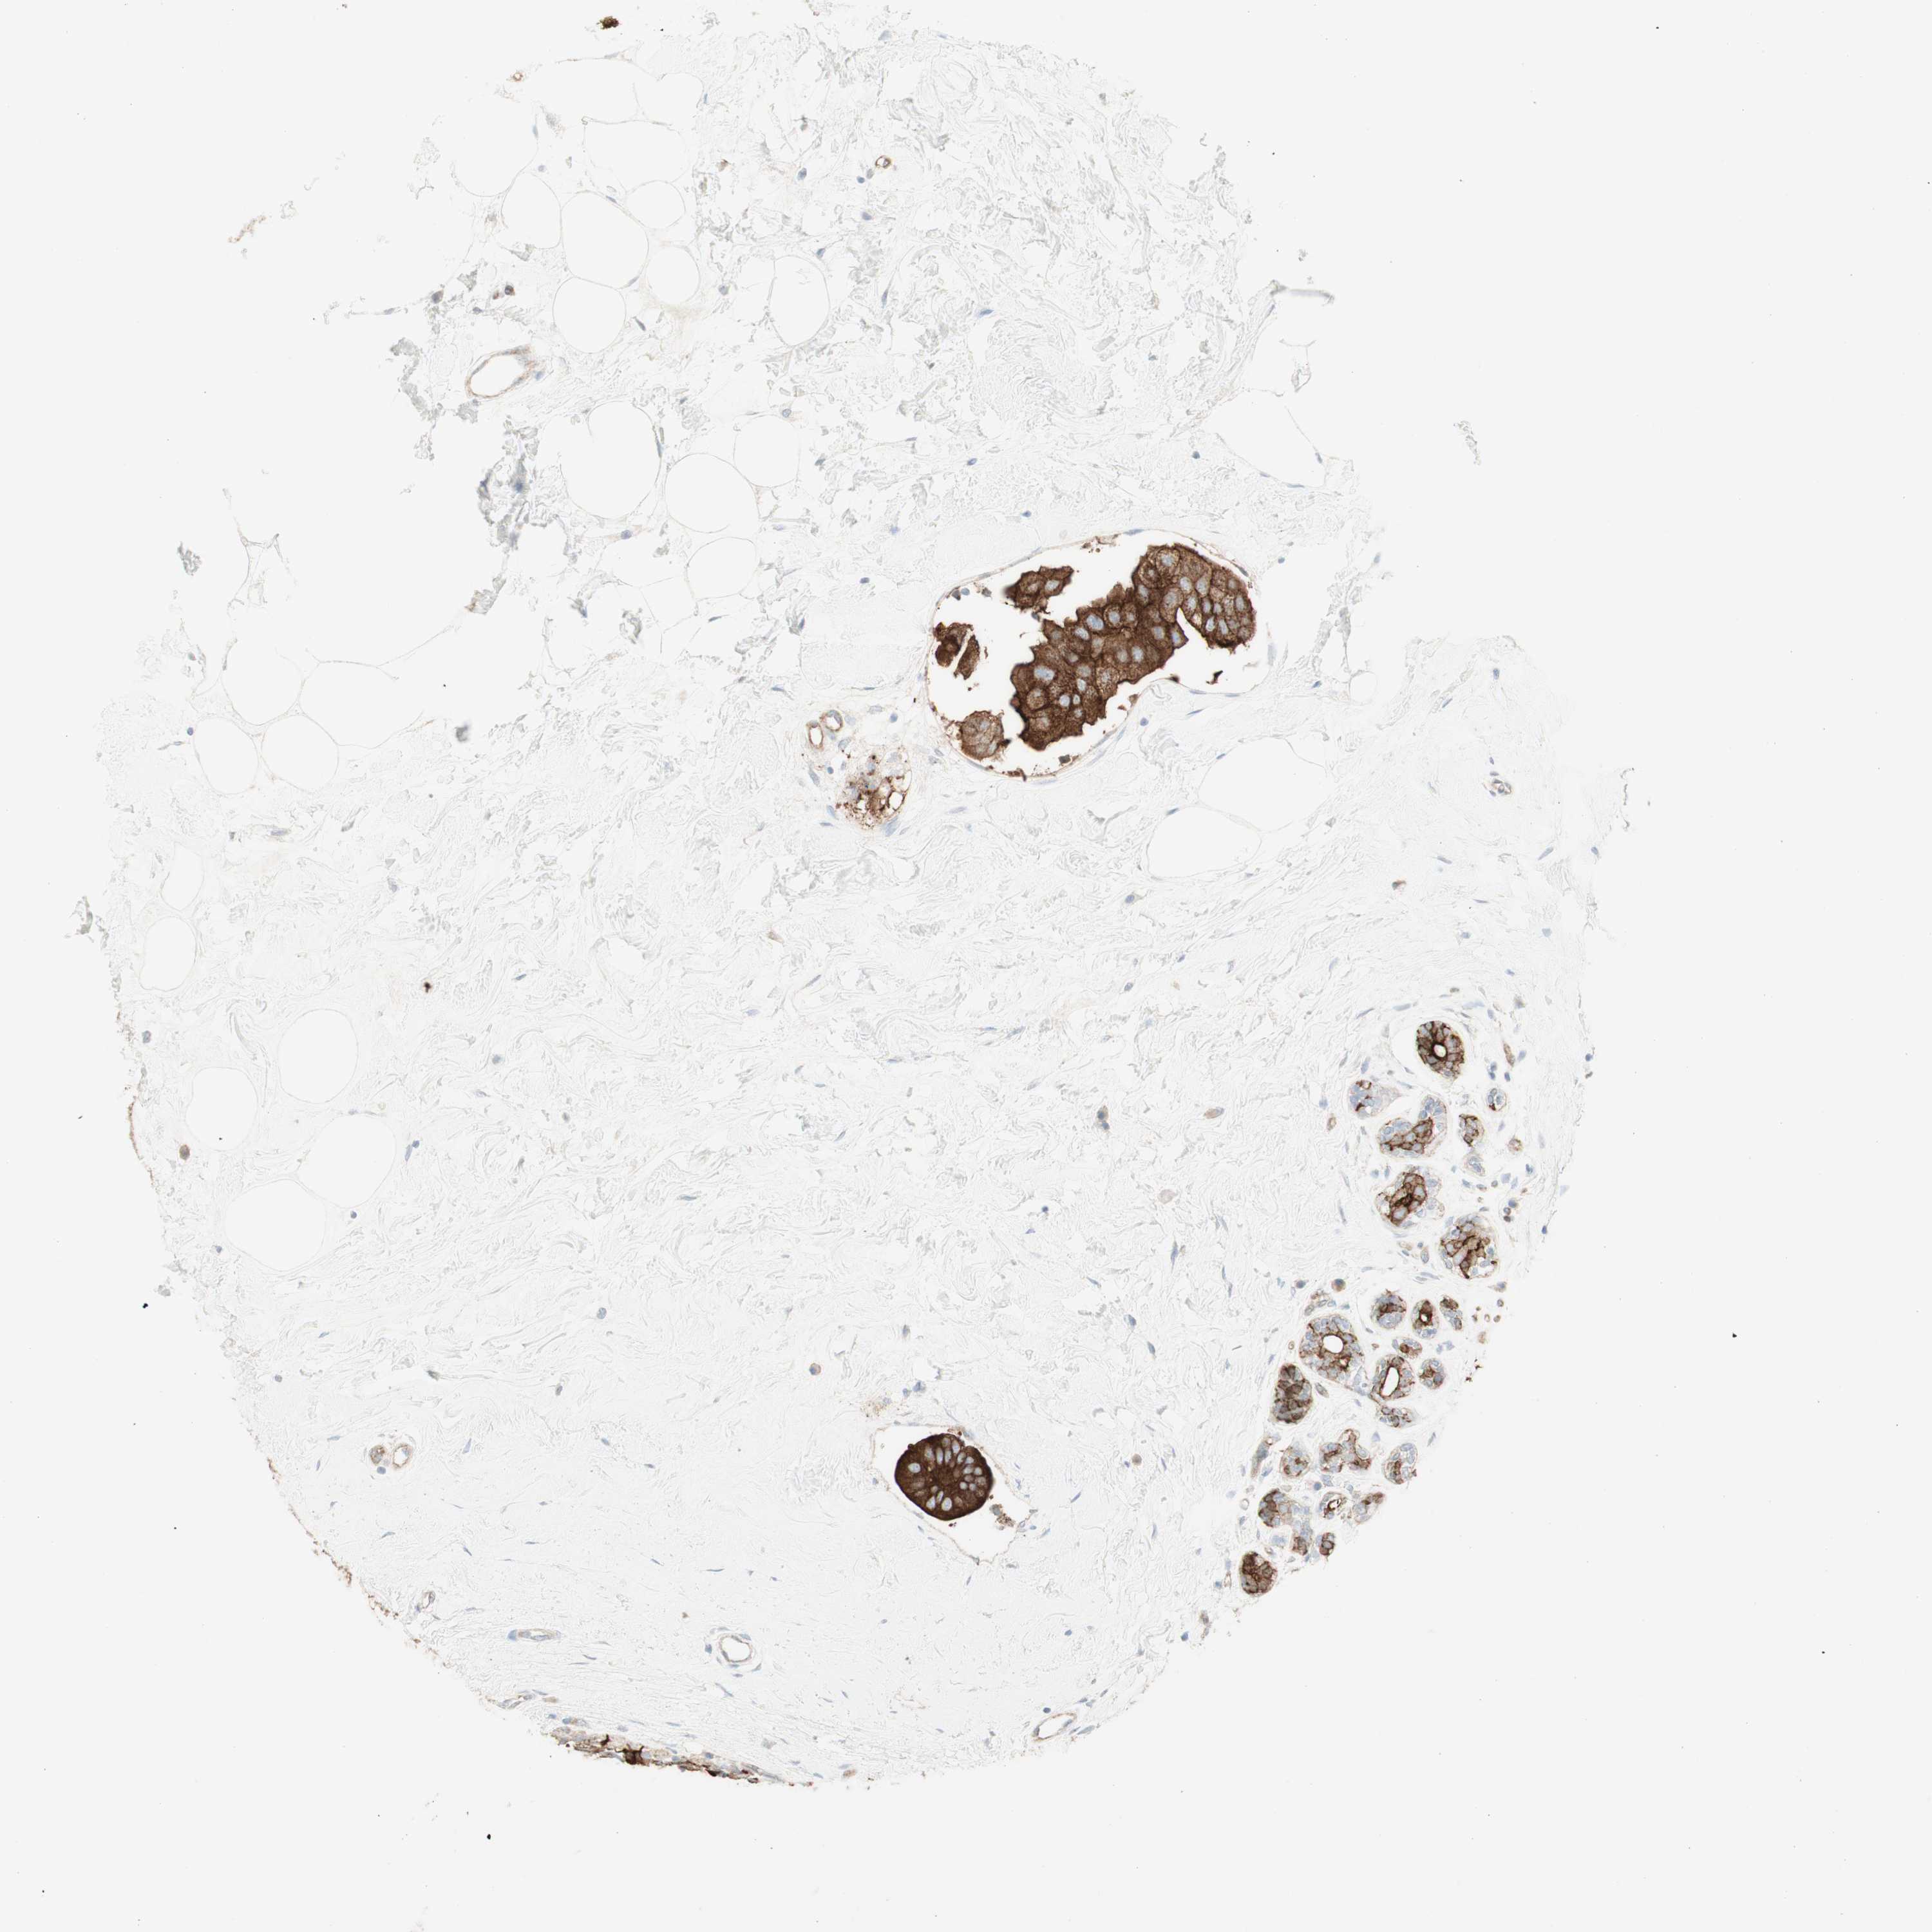

CANCER BREAST CANCER Show tissue menu

BRCA TCGA BRCA VALIDATION PROTEIN EXPRESSION